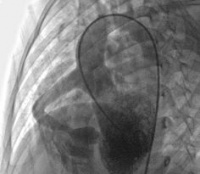

X线检查肺栓塞可引起肺动脉高压征象,多发性小的肺栓塞呈支气管肺炎样弥散的浸润阴影,较大的栓塞则发生肺梗死呈楔形阴影。肺血管造影可显示直径0.5mm以上的血管能直接看到栓塞的部位和范围。也为手术治疗作好准备。

X线检查发现密度均匀边界清楚的团块阴影,病灶内偶有很少的钙化,阴影随深吸气扩大深呼气缩小。 肺动脉造影MRI检查可清楚地了解动静脉瘘的位置,单发或多发,也可为手术作好准备。